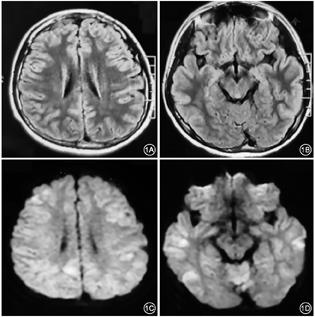

血常规:白细胞14.30 × 109/L,中性粒细胞0.74,淋巴细胞0.158,C反应蛋白3.9 mg/L。单纯疱疹病毒Ⅰ型IgM阴性,EB病毒阴性,降钙素原0.392 ng/ml。腰穿脑脊液白细胞39×106/L,单个核细胞37×106/L,多核细胞2×106/L。头颅MRI示:双侧脑皮层多发异常信号(图1)。脑电图:异常脑电图,可见弥漫性不规则慢波。予以静脉阿昔洛韦(10 mg/kg q8h,共14 d),甘露醇,静注人丙种球蛋白(0.4 g/kg/d,共5 d)等对症治疗。入院第3天,患者出现精神行为异常,兴奋,入睡困难,且逐渐加重,考虑自身免疫性脑炎不除外,予以加用静脉甲泼尼龙琥珀酸钠治疗(1000 mg/d,共3 d, 500 mg/d,共3 d),后减量改口服激素。患者体温恢复正常,无抽搐;复查脑电图未见异常。复查头颅MRI:颅内多发病灶较前减轻。为一步明确诊断,送检血与脑脊液自身免疫性脑炎抗体谱、副肿瘤神经综合征抗体谱(未一医学检验实验室),包括抗NMDAR、 CASPR2、AMPA1、AMPA2、LGI1、GABABR、 GAD65、Hu、Yo、Ri抗体等,结果均为阴性。患者症状进一步好转后出院。3个月后患者为求明确诊治就诊于北京协和医院神经科脑炎门诊,患者症状已完全消失,无明显不适,复查头MRI未见异常,原有病灶消失。根据中国医学科学院北京协和医院脑炎病因诊断一体化方案,调取剩余的冻存脑脊液样本进行病原体二代测序(next-generation sequencing,NGS)(未一医学检验实验室),检测到人类疱疹病毒7型(HHV-7)特异性序列7条(图2),平均测序深度1.1740,基因组的覆盖度0.2816%;通过生信分析可排除背景菌及其他可能污染,综合判断结果置信度高。后行PCR验证试验,HHV-7阳性。

头颅MRI示:双侧脑皮层多发异常信号。脑电图:可见弥漫性不规则慢波。腰穿脑脊液白细胞39×106/L,单个核细胞37×106/L,自身免疫性脑炎相关抗体检测阴性。常规病原体检测结果阴性,后根据脑炎病因诊断一体化方案,行脑脊液病原体二代测序,检出人类疱疹病毒7型(HHV-7),并予以PCR验证。